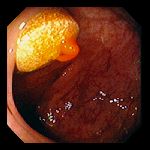

- 38-летний человек потерял сознание в аэропорту. Установлена передозировка наркотических средств. При обзорной рентгенографии брюшной полости обнаружены инородные тела толстого кишечника.

- При колоноскопии были обнаружены капсулы, заполненные наркотическим веществом (на фото удаление капсулы петлей).

- На фото видны 13 капсул из общего количества, составившего 31 капсулу.